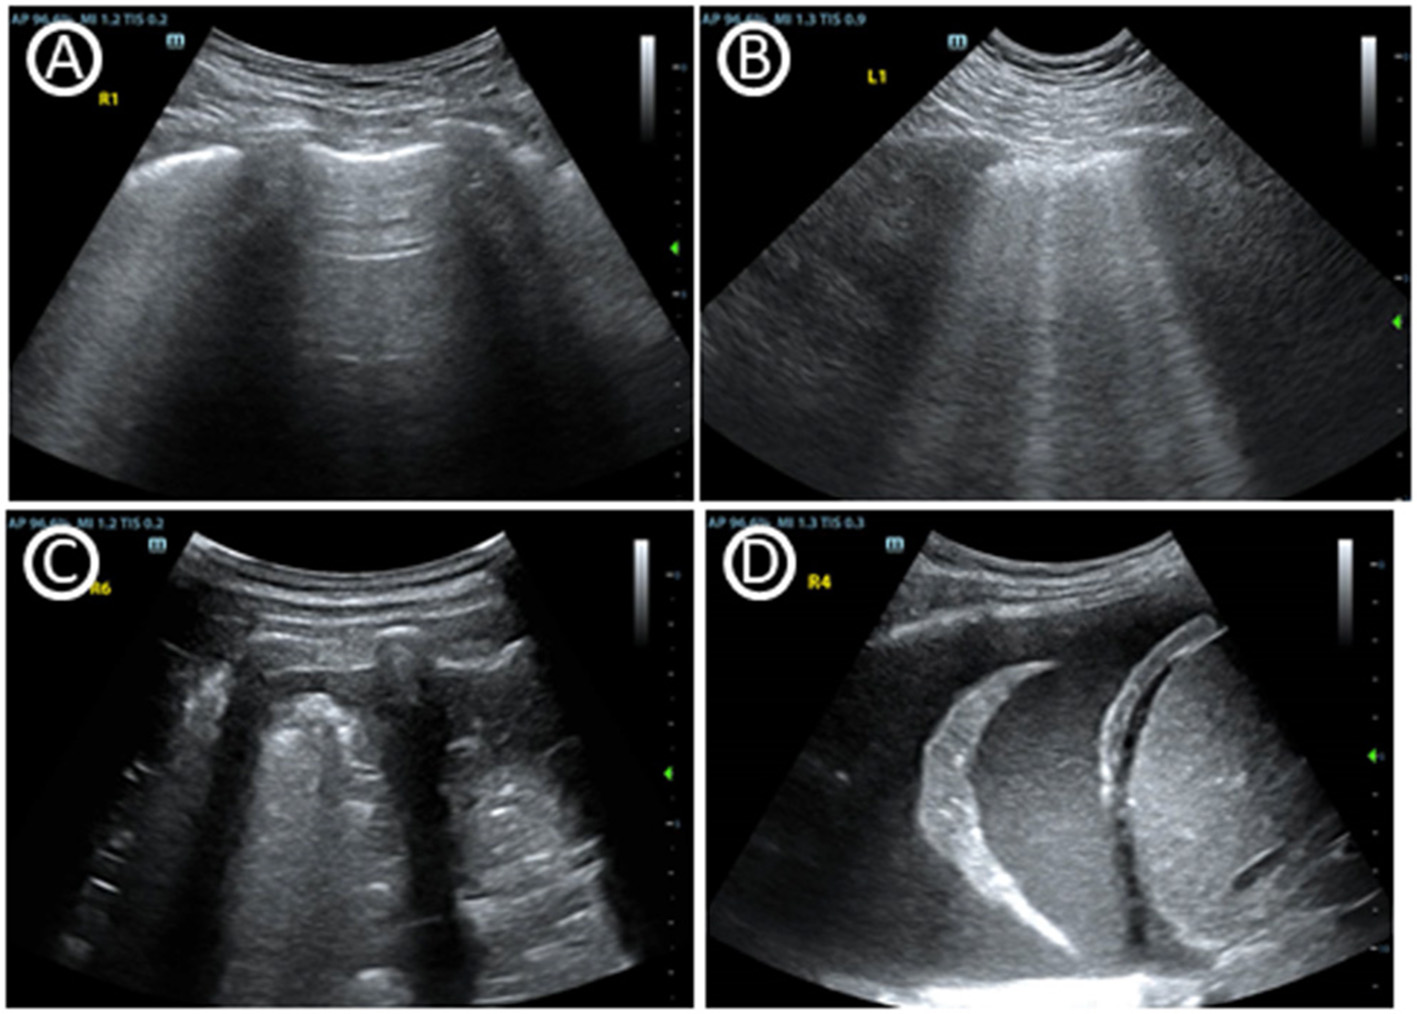

Acute kidney injury (AKI), shown as oliguria or elevated serum blood urea nitrogen or creatinine, is common in ICU. Renal ultrasound may help clinician to define the circumstances bedside (Figure 3) (52, 53). The CCE that was mentioned previously could guide shock differentiation and volume status assessment. Renal ultrasound could evaluate renal size, echogenicity, vascularity, and the presence of urinary tract obstruction, imaging both kidneys and the bladder. Resistive index (RI) of the arcuate and interlobar arteries was widely studied as a potential objective marker for renal pathology, and was shown to be a prognostic factor (54, 55). RI showed advantage in detecting hypoperfusion due to hypovolemia and hemodynamics titration to improve renal blood flow (56). However, although RI has been studied extensively, its interpretation remains particularly complex and is highly dependent on the clinical setting (57). Renal contrast-enhanced ultrasonography can be used to non-invasively evaluate renal macrocirculation and microcirculation in critical ill patients. Decrease in renal blood flow, particularly cortical blood flow, may be observed in septic AKI through the technology and may contribute to its development (58).

Figure 3

Images of multiorgan ultrasound. (A) Normal doppler tracing of the interlobar vessels in renal ultrasound. The renal resistive index can be measured using the maximal and the minimal arterial velocity during the cardiac cycle. (B) Renal contrast-enhanced ultrasonography. (C) Dilated fluid-filled bowel loops that indicates small bowel obstruction. (D) Blood flow curve of superior mesenteric vein. (E) Optic nerve sheath diameter, which can help to predict intracranial pressure. (F) Cerebral blood flow velocity of middle cerebral artery accessed by transcranial doppler ultrasonography.

In addition to the Focused Assessment with Sonography in Trauma protocol (FAST) used in trauma patients, there is an additional focus on gastrointestinal (GI) failure or dysfunction that is evaluated by ultrasound (59–61). There is currently a lack of universally accepted criteria for gastrointestinal failure or dysfunction in critical care. Gastrointestinal ultrasound can provide its anatomical and functional information through the lumen, wall and the surrounding structures of the stomach and bowel. Evaluation of functional processes like peristalsis and blood flow may be used in combination (Figure 3) (62). Monitoring GI function through gastrointestinal ultrasound may effectively assess acute gastrointestinal injury, predict feeding intolerance and lead to appropriate therapeutic interventions. An interdisciplinary group of European experts also summarizes use of gastrointestinal ultrasound in identifying causes of acute abdomen like bowel obstruction, gastrointestinal perforation and acute ischemic bowel disease (Table 2) (63). Just like other ultrasound types, adequate training is needed to use and interpret the ultrasound images correctly. In gastrointestinal ultrasound, image quality was easily influenced by air-filled bowel or obesity.

Neurological Ultrasound

In the clinical management of several neurological diseases, intracranial pressure (ICP) is an important monitoring indicator. Since ICP is not conveniently monitored, non-invasive monitoring of ICP (nICP) may be helpful to improve the clinical management of these conditions. Cerebral blood flow velocity (FV) accessed by Transcranial Doppler ultrasonography (TCD) is an effective technique (64, 65). The optic nerve sheath diameter measurement may also reveal that a congested papilla develops with optic disc elevation when the increase in ICP persists (Figure 3) (66, 67). Neurological ultrasound combing with LUS also helps when intracranial hypertension and severe lung damage coexist in the same clinical scenario, since recommending ventilation strategies in ARDS may potentially increase intracranial hypertension. Combined use of LUS with optic nerve sheath diameter assessment and TCD can contribute to a tailored brain-protective ventilation strategy (68). However, some studies showed TCD may errorly affect clinical decision-making. Perhaps it is because of the different elastic modulus of different intracranial tissues that ICP cannot be measured like the liquid pressure in a closed container. ICP monitoring based on TCD is a potential research direction, but its clinical value is still further verified.